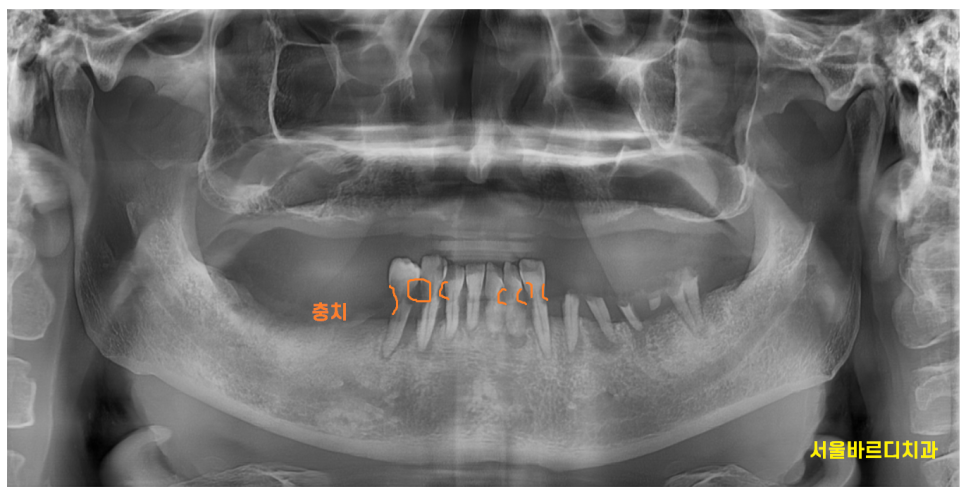

틀니를 10년 가까이 써서

뼈가 많이 흡수되었는데요.

아래 임플란트는 문제 없었지만

윗니 어금니는 ct를 통해 남아있는 뼈를

분석하였습니다.